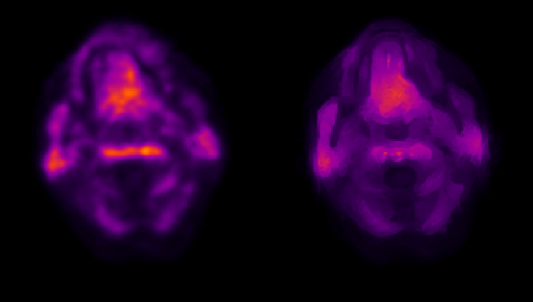

MICSI-PET is a turnkey upgrade that dramatically enhances PET image quality by using the MRI as an anatomical guide. This process does not require any additional imaging as all patients should have received an MRI prior to amyloid PET imaging. Operationally, this upgrade removes the primary barrier for scaling Alzheimer’s therapies by (1) enabling high-end PET imaging on low-end or aging PET scanners; (2) enabling shorter PET examinations leading to greater throughput; (3) minimizing ambiguity of positive/negative amyloid PET imaging by showing clearer boundaries between gray and white matter:

Figure: Coregistered conventional PET and MICSI-PET amyloid images across a range of amyloid burdens, highlighting differences in apparent cortical sparing: left, amyloid-negative with strong gray/white contrast; right, amyloid-positive with reduced gray/white contrast.